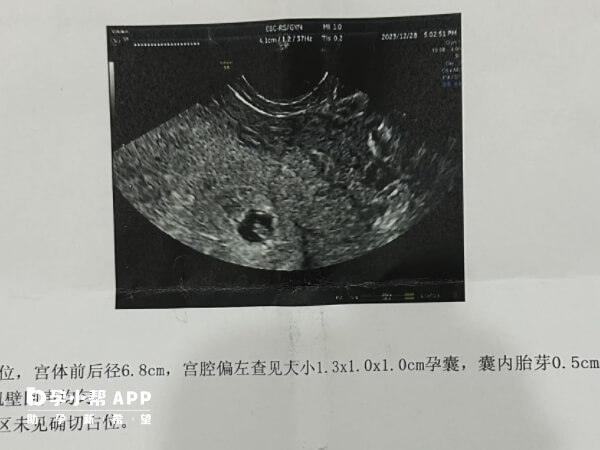

临床上,胎停育的超声检查结果常表现为枯萎卵,有胚芽无心管搏动,有形态不规则的胚芽或胎儿存在于孕囊。如果大家想要了解,胎停育之后还要继续观察一周的原因都有哪些,可参考下列内容了解。

超声检查可能存在误差,如胎儿位置不佳、仪器敏感度差异等,可能导致误判胎停。观察一周后再次检查,可提高诊断准确性,避免过早终止妊娠;

部分女性因月经周期不规律,实际受孕时间可能晚于预期。孕8周前B超可能无法检测到胎心,观察一周可排除因孕周计算错误导致的假性胎停。